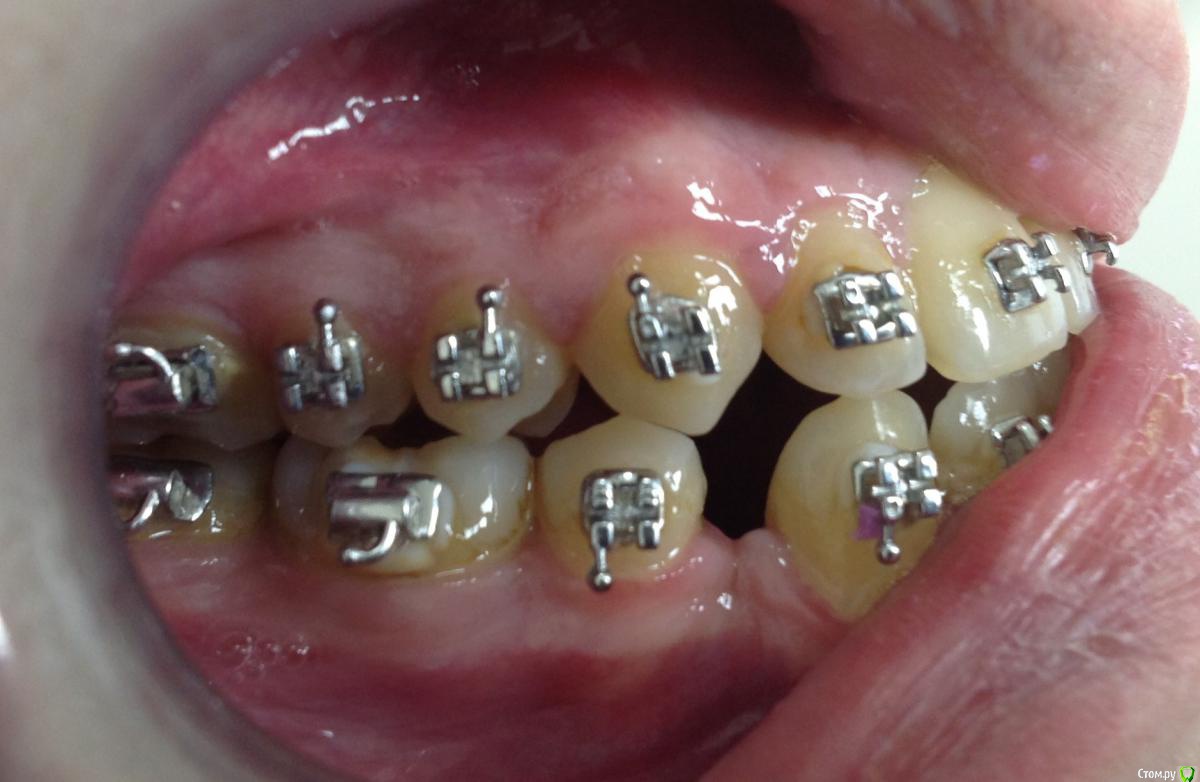

KoroNa Опубликовано 13 января, 2015 Поделиться Опубликовано 13 января, 2015 Здравствуйте. Опыт у меня совсем небольшой, можно даже сказать никакой на данном этапе. Пациент достался "по наследству" от подруги. Приехал учиться в наш город, она и пристроила мне. Я делала свое дело, меняла лигатурки, зная, что пациент периодически ездит в свой город и будет контроль лечения со стороны моей коллеги. А та, не долго думая, в декрет укатила с двойней. Когда увидела пациента, то как РАДА НЕ БЫЛА - ничего не сказать.3класс. вертикальный тип роста. Явные признаки к комплексному орто\хир лечению. Но она взялась, пожалела\попросили.....удалила премоляры на н\ч и начала дистализацию. Никаких ТРГ и моднлей в помине нет, да и я еще когда брала его даже фотографии не делала.Не хочу на форуме ругаться, но пациент "какашка" .......гигиенты нет как в полости рта, так и на лице...пропуски приемов....и т.д.НО! Подруге пообещала....Я сразу написала, что опыта ноль, только благодаря нашим лекторам стала сейчас обращать внимание на симметрию, на сустав и т.д. И вот, заходит пациент, на очередную смену лигатур, такой красивый в кабинет и что я вижу.....нижняя челюсть смещена влево, явная асимметрия. Куда мои глаза и мозги смотрели. Очень прошу помочь мне советами, что сейчас нужно сделать, с чего начать Ссылка на комментарий

KoroNa Опубликовано 20 января, 2015 Автор Поделиться Опубликовано 20 января, 2015 Думаю паниковать пока рано. Такое иногда бывает при значительном перемещении зуба/зубов, когда возникают контакты бугор-в-бугор, а н.ч отвечает компенсаторным смещением в ту или иную стогону. Если ЦЛ н.ч при максимальном оркрывании рта мигрирует, то всеОК. В любом случае проведите полную диагностику, а ОПТГ сейчас сделайте в положении ЦО (при полном/максимальном смыкании зубов). Это даст возможность оценить симметрию СГ.PS с какой целью стоит лингвальная кнопка на в.ч, носит ли пациент эластики и если да то как?Здравствуйте.Центральная линия при максимальном открывании рта практически "централизуется", но там есть еще и смещение ЦЛ из-за миграции резцов влево."ОПТГ сейчас сделайте в положении ЦО (при полном/максимальном смыкании зубов" - т.е. объяснить пациенту чтобы сомкнул рот на все зубы как смыкает обычно? не нужно смещать челюсть и делать прикусной шаблон?Кнопка справа на 6ом моляре применялась для устранения перекрестной окклюзии. пациент оторвал замок и около месяца не появлялся на прием. вот зуб и уехал. Ссылка на комментарий

KoroNa Опубликовано 23 января, 2015 Автор Поделиться Опубликовано 23 января, 2015 Кнопка справа на 6ом моляре применялась для устранения перекрестной окклюзии. пациент оторвал замок и около месяца не появлялся на прием. вот зуб и уехал. Что значит "уехал" , а конкретнее куда?Спасибо за ваши комментарии. Зуб 1.6 "ушел" в небную сторону -палатиноокклюзия, если не ошибаюсь. Ссылка на комментарий

Maverick Опубликовано 1 марта, 2015 Поделиться Опубликовано 1 марта, 2015 (изменено) Переместить зубы в положение которое было запланировано изначально, справа поработать с перемещением, потом слева дотянуть, чтобы получить хорошие контакты, плюс полноразмерную стальные дугу можно расширить немного если есть необходимость в этом. Фото фронтальное сделано неправильно и дает неверную информацию, искажая данные. Хорошо было бы взглянуть что было до начала лечения. Хороших окклюзионных контактов все равно не получится в итоге. Изменено 1 марта, 2015 пользователем Maverick Ссылка на комментарий